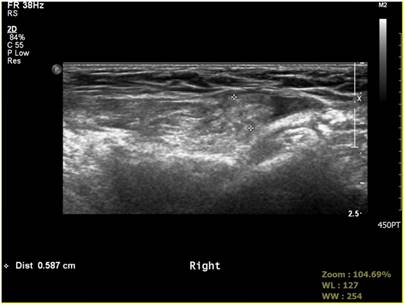

Fig 6

Negative sonographic finding of processus vaginalis.

The accuracy of sonography in our study was 64.5%. In our study, 35 out of 95 patients without abnormal findings in the preoperative sonography showed positive PPV. The preoperative sonography had higher false negative rate base on laparoscopic finding for sensitivity. The higher PPV rate in our study than previously reported PPV rate might be due to the sensitivity of laparoscopic examination. Broad multicenter study with more enrolled patients might lead to higher accuracy of preoperative sonography. Also, large scale studies with long-term follow-up are needed to determine the exact incidence of metachronous hernia in pediatric inguinal hernia patients. Expansion of laparoscopic surgery for pediatric inguinal hernia suggests that pediatric surgeons should do long-term follow-up of patients. We also need more studies on natural history of PPV because preoperative sonography alone is insufficient to confirm the status of PPV (Fig. 6, Fig. 7).

The accuracy of sonography from well-known studies was of a similar figure to the accuracy of 64.5% resulted in our study. The accuracy of sonography can be affected by ultrasound resolution, diagnostic criteria, and skillfulness of the operator. In our study, sonography was performed by one genitourinary radiologist. The measurement of the inner ring size was not performed on PPV. We set abnormal shading on sonography as a positive finding. By comparing sonography results with findings of laparoscopy, we were able to better understand the sonographic accuracy of contralateral PPV (Fig. 4, Fig. 5).